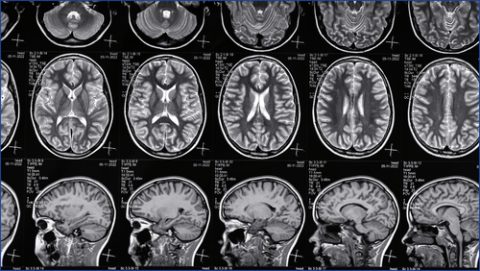

PTE can develop in people who have experienced a Traumatic Brain Injury (TBI). A traumatic brain injury is one of the known causes for developing epilepsy and we regularly support people who have developed epilepsy because of a traumatic brain injury.

There is currently no method to predict or prevent epilepsy in those who have experienced a traumatic brain injury. However, earlier this year, the research team at FutureNeuro - led by Dr. Tobias Engel - identified a receptor on immune cells in the brain (called P2X7) which plays a role in brain inflammation after injury.

The research went on to suggest that potentially targeting this receptor with medications could be effective in reducing or even preventing epilepsy occurring in TBI. You can read more on this by visiting the 'News' section of our website.